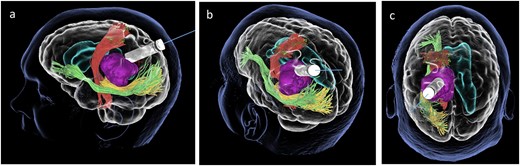

We hereby present the case of a 32-year-old gentleman referred to the neuro-oncology service with an 8-months history of left sided headaches, dizziness, and blurred vision. MRI head demonstrated a 50 × 52 × 51 mm lesion in the posterior horn of the left lateral ventricle, with extension into the periventricular white matter (Fig. 1). Following multi-disciplinary discussion, a plan was made for the patient to undergo a minimally invasive approach for resection of this lesion. Pre-operative cortical and subcortical mapping was performed with navigated transcranial magnetic stimulation (nTMS) and diffusion tensor imaging (DTI). The best trajectory was defined taking into consideration the localization of the cortico-spinal tract (CST, red), the inferior fronto-occipital fasciculus (IFOF, green) and the optic radiations (OR, yellow) (Fig. 2).

Lateral (a), ¾ lateral (b), and posterior (c) views of the pre-operative virtual 3D reconstruction model. The tumour (purple) is reached by the tubular retractor (white) and encircled by the associated white matter tracts: the CST (red) superiorly and anteriorly, and the IFOF (green) and the OR (yellow) that are located inferiorly, laterally, and posteriorly to the lesion.